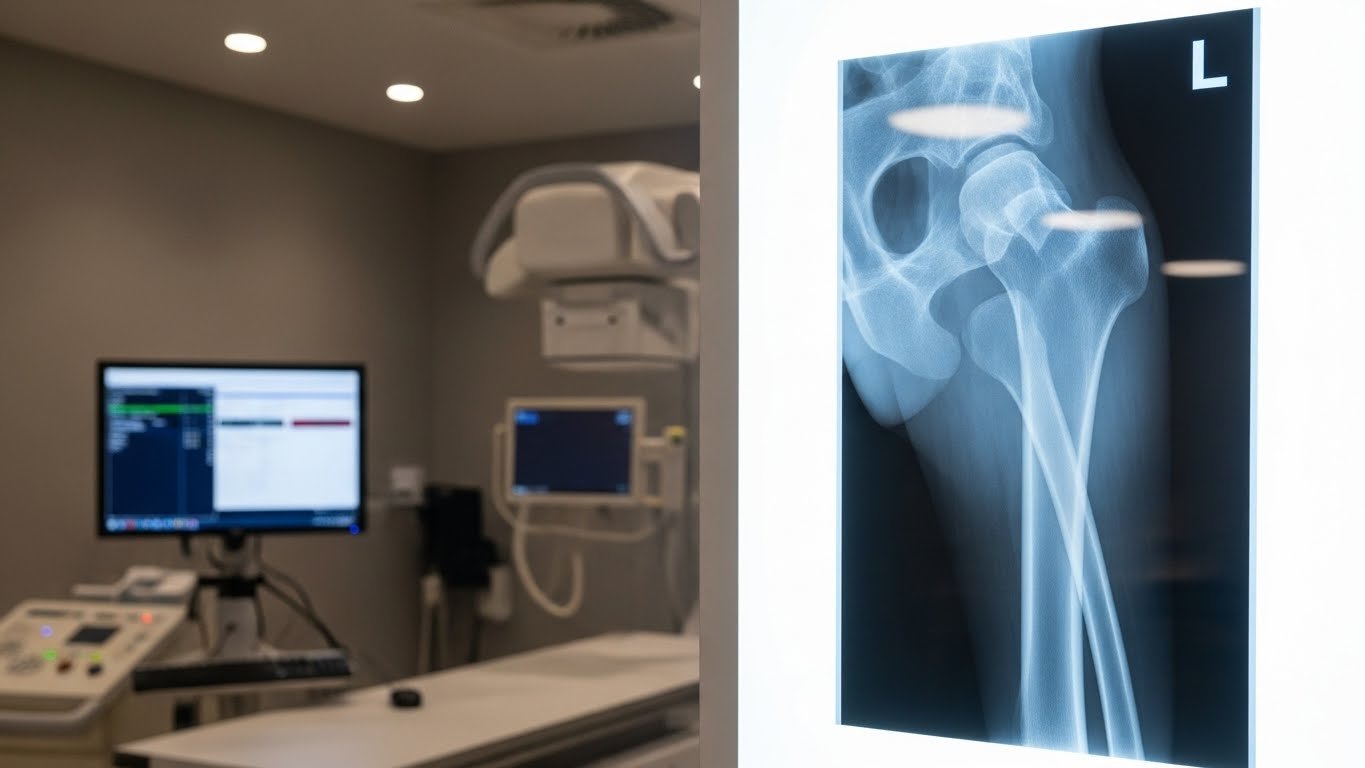

Une radiographie du fémur est un examen d’imagerie médicale qui utilise les rayons X pour visualiser l’os de la cuisse dans son intégralité, de l’articulation de la hanche jusqu’au genou. Cet examen permet aux médecins d’observer la structure osseuse, de détecter d’éventuelles fractures, infections ou anomalies, et d’évaluer l’état de santé de votre fémur.

Le fémur est l’os qui compose votre cuisse. C’est le plus long et le plus résistant du corps humain, capable de supporter jusqu’à 30 fois le poids de votre corps lors de certains mouvements. Il se compose de trois parties principales :

- La tête fémorale : partie supérieure arrondie qui s’insère dans la hanche

- Le col du fémur : zone fragile entre la tête et le corps de l’os

- La diaphyse : le long corps cylindrique de l’os

- Les condyles : extrémités inférieures qui forment l’articulation du genou

Comprendre cette anatomie aide à mieux saisir pourquoi certaines zones, comme le col du fémur, sont particulièrement vulnérables aux fractures, surtout chez les personnes âgées.